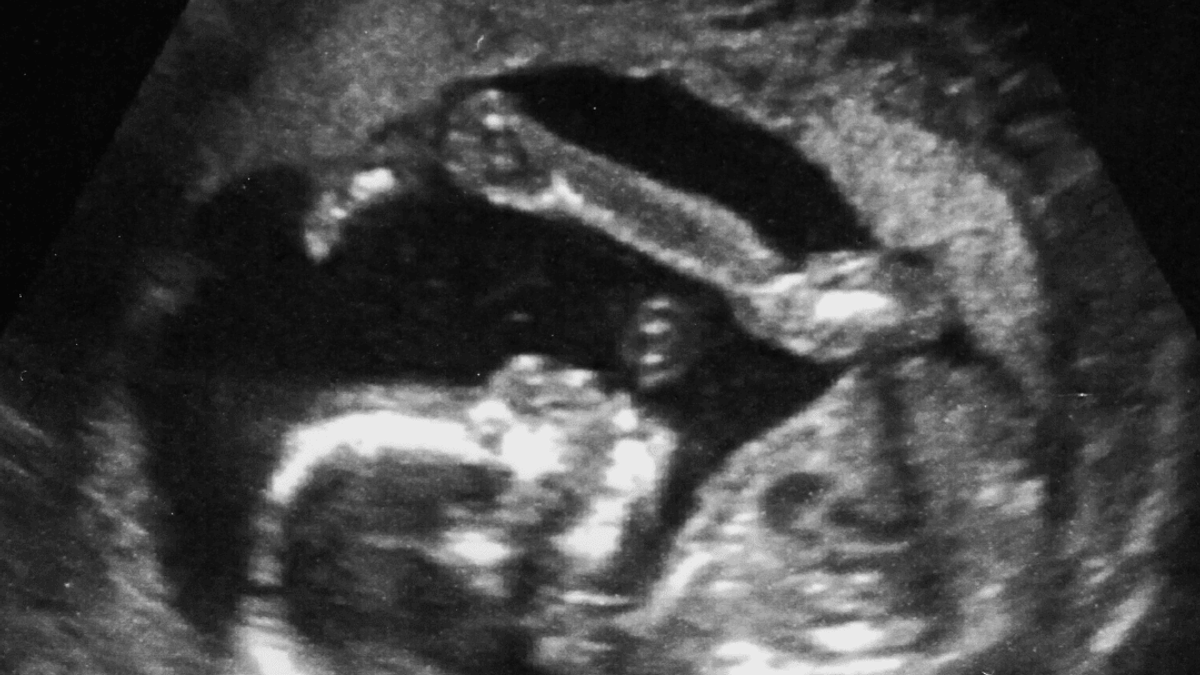

Ik kon de artsen niet vertellen, wanneer ik zwanger geraakt zou kunnen zijn, aangezien ik nog steeds de pil slikte en tijdens m’n stopweken steeds bloedingen heb gehad. Bij het maken van de echo om te kijken of het vruchtje niet buitenbaarmoederlijk zat (vanwege de pijn die ik had) en om te kijken hoever ik zwanger was, konden ze niet doorgaan, doordat de pijn te heftig was. Wel konden ze zien dat het hartje klopte en vanuit mijn hcg konden ze opmaken dat ik rond de 17 weken zwanger was.

Deze reacties waren allemaal heel erg positief. De kinderen, 12 en 6 jaar oud, vinden het leuk om een klein broertje te krijgen (ja het was al te zien bij die eerste echo dat het een jongen is).

Toen kwam schok 3 waar ik eigenlijk nog steeds in zit, maar snel uit moet. Eind december had ik een echo en vertelde de aardige mevrouw daar dat ik al 19+4 dagen in verwachting was.

Daar vertelt de aardige mevrouw dat m’n baby er gezond uitziet en goed groeit, alleen denkt zij aan een uitrekende datum rond half mei. Ik heb 19 weken niet geweten van het leven dat in mij aan het groeien is en ik heb helemaal geen symptomen gehad. Ja, 4 of 5 kilo aan gekomen, maar ja ik eet ook meer sinds maart en beweeg minder dus dit vond ik niet gek.